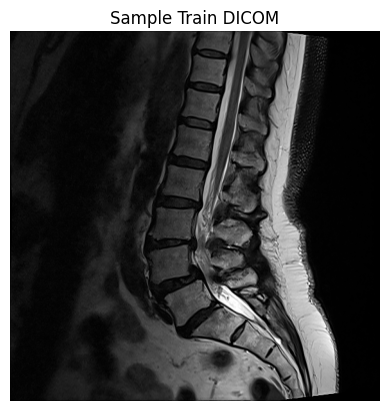

Figure (1) displays sagittal and axial MRI slices from two sample images in the dataset. The sagittal view depicts the lumbar vertebrae, intervertebral discs, and spinal canal in longitudinal section, allowing assessment of disc height loss and spinal stenosis. The axial view provides a transverse cross-section of the spinal canal and adjacent structures. Together, these perspectives enable a comprehensive evaluation of lumbar spine degeneration.